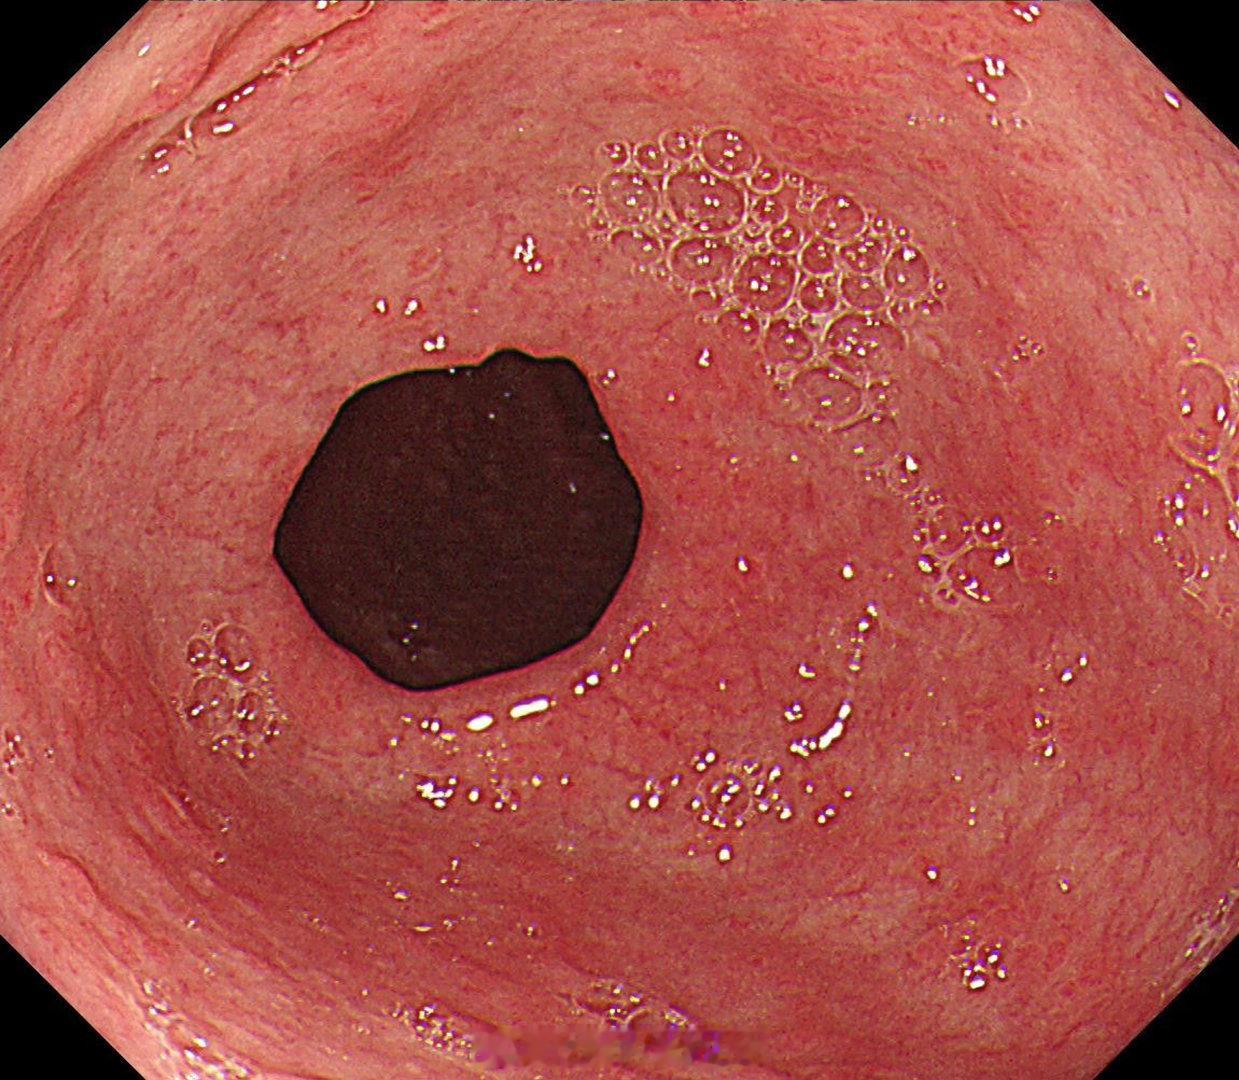

这是个常州来找我会诊的疑难杂症,当地觉得萎缩一塌糊涂,但是活检也没有提示啥病因,一开始我接诊也觉得是自身免疫性胃炎,但是抽血指标都不符合,最后在几块残余正常黏膜表现中看到了点蛛丝马迹,活检加上masson染色确诊是胶原性胃炎,以前不认识的时候这个世界都没这个病,一旦会诊断以后,满眼都是这类病[允悲][允悲][允悲]

这是个常州来找我会诊的疑难杂症,当地觉得萎缩一塌糊涂,但是活检也没有提示啥病因,一开始我接诊也觉得是自身免疫性胃炎,但是抽血指标都不符合,最后在几块残余正常黏膜表现中看到了点蛛丝马迹,活检加上masson染色确诊是胶原性胃炎,以前不认识的时候这个世界都没这个病,一旦会诊断以后,满眼都是这类病[允悲][允悲][允悲]